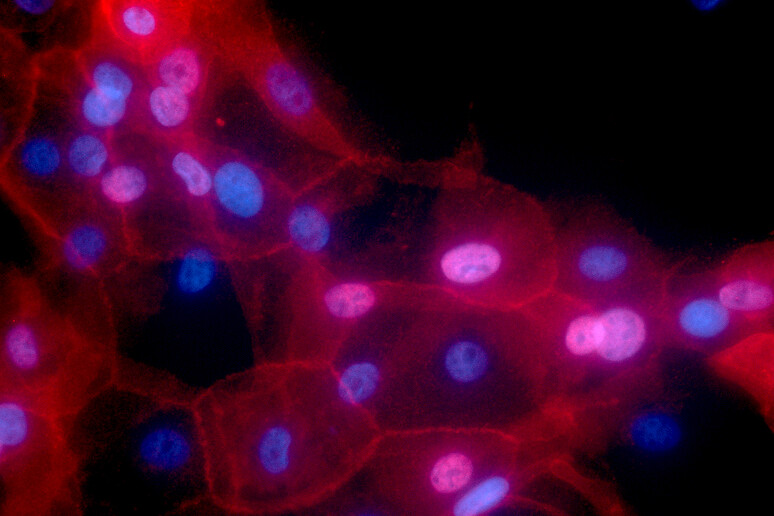

Un’altra scoperta premiata nel 2016 con il Nobel per la Medicina (consegnato a Yoshinori Ohsumi) potrebbe aprire una nuova frontiera nella lotta contro il cancro: è l’autofagia, il processo con cui le cellule del nostro corpo ‘cannibalizzano’ alcune loro componenti, per riciclare parti danneggiate ed eliminare patogeni. Disfunzioni in questo meccanismo sono legate allo sviluppo del cancro e di molte altre malattie, consentendo alle cellule tumorali di sopravvivere in condizioni estreme e resistere all’azione dei farmaci.